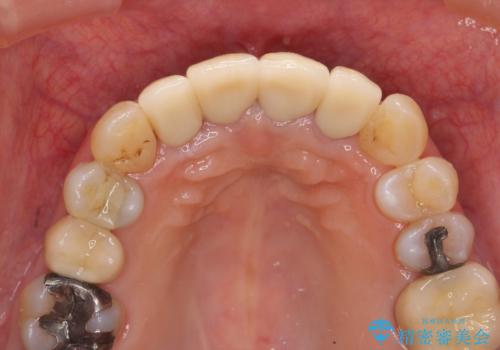

老朽化した前歯のセラミック治療やりかえ

- 20年前に治療した前歯のセラミッククラウンが老朽化し見た目の改善を求めて来院されました。

不十分な根管治療を含めたセラミッククラウンのやりかえ治療を計画します。

クラウン治療は経年的に歯ぐきの位置が変わり汚れが溜まってしまったり、見た目が悪くなるなどの問題が出てくることがあります。

現在の歯ぐきの位置できっちりと仕上げることで見た目の改善が達成されました。